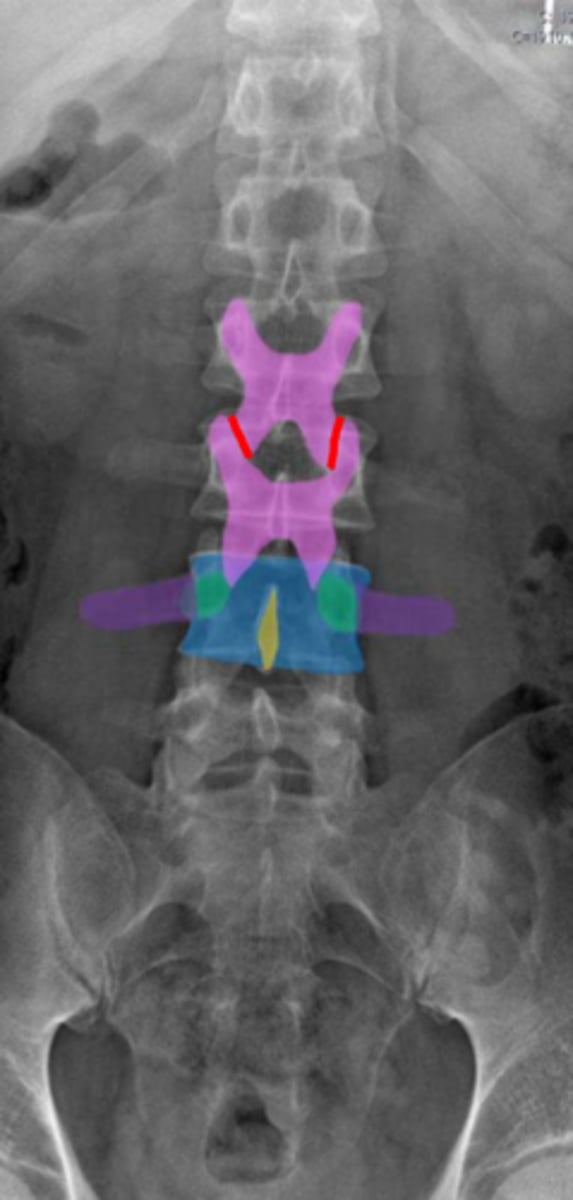

lumbar

What vertebrae is being examined?

lumbar vertebral body

Identify the blue structure

pedicles

Identify the green structure

transverse processes

Identify the purple structure

spinous processes

Identify the yellow structure

joint space between superior and inferior articulating facets

Identify the red line